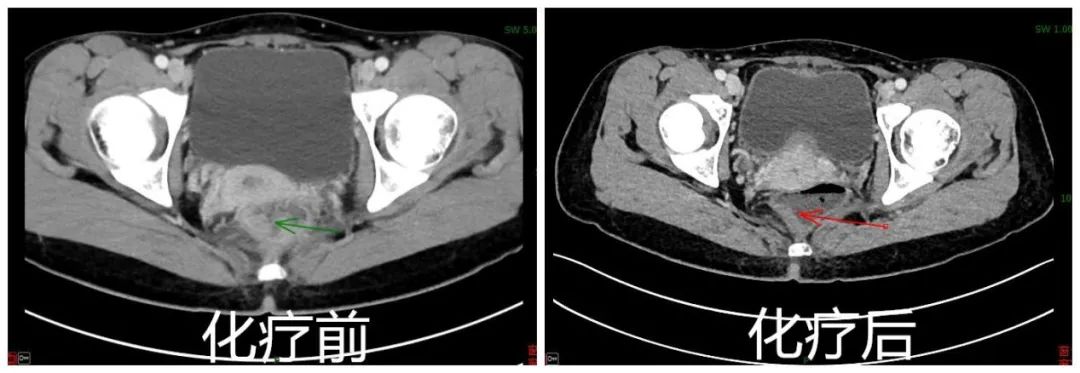

CT检查结果新辅助化疗前后对比